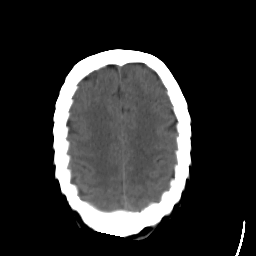

Stroke CT #1 -- Slice #19

[Home][Help][Clinical] Slice 19